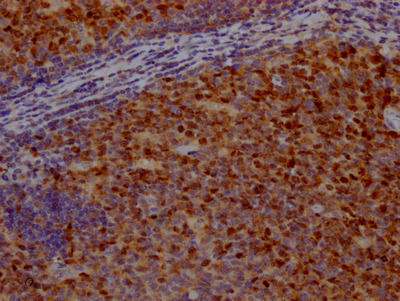

IHC image of CSB-RA209144A0HU diluted at 1:100 and staining in paraffin-embedded human tonsil tissue performed on a Leica BondTM system. After dewaxing and hydration, antigen retrieval was mediated by high pressure in a citrate buffer (pH 6.0). Section was blocked with 10% normal goat serum 30min at RT. Then primary antibody (1% BSA) was incubated at 4℃ overnight. The primary is detected by a Goat anti-rabbit IgG polymer labeled by HRP and visualized using 0.05% DAB.